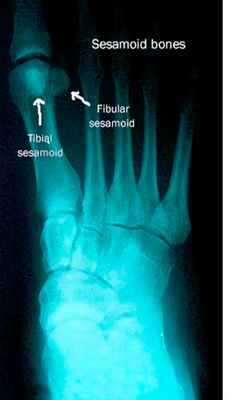

На стопе под 1 плюснефаланговым суставом имеются две сеcамовидные кости. Каждая кость может состоять из двух долей, которые отделены друг от друга, что считается вариантом нормы. Сесамовидные кости представляют собой опору для сухожилий сгибателей большого пальца. Сесамовидные кости своей массой увеличивают расстояние от сухожилия до центра вращения 1 плюсне-фалангового сустава. Происходит увеличение рычага силы сгибания пальца и увеличение момента мышц, которые сгибают большой палец, что необходимо для отталкивания от опоры.

Рис. 2. Рентгенограмма правой стопы. По внутреннему краю расположена большеберцовая или медиальная сесамовидная кость, по наружному краю – малоберцовая или латеральная сесамовидная кость

Сесамоидит является распространенной причиной метатарзалгии Метатарзалгия Метатарзалгия – общий термин, означающий наличие болевых ощущений в плюснефаланговых суставах. (См. также Обзор болезней стопы и голеностопного сустава (Overview of Foot and Ankle Disorders). Прочитайте дополнительные сведения . Две полулунные сесамовидные кости участвуют в обеспечении локомоторной функции стопы. Медиально расположена большеберцовая сесамовидная и латерально – малоберцовая сесамовидная кость. Травма или смещение сесамовидных костей при повреждении стопы (например, латеральное смещение сесамовидной кости при отклонении большого пальца кнаружи) может привести к появлению болей. Сесамоидит особенно часто встречается у танцоров, бегунов, и людей с куполовидной стопой, или при использовании обуви с высоким каблуком. Многие люди с бурситом большого пальца стопы Бурсит большого пальца стопы Заболевание сопровождается выступанием медиальной части головки 1-ой плюсневой кости. Причиной его являются частые аномалии положения 1-ой плюсневой кости или большого пальца, в частности вальгусная. Прочитайте дополнительные сведения имеют большеберцовый сесамоидит.